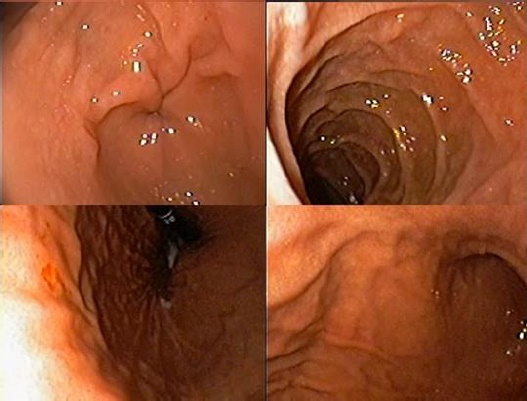

Durante su protocolo de estudio se realizaron estudios paraclínicos con único hallazgo significativo de Blastocystis spp 28-30 por campo al coproanalisis (Tabla 1). Cuenta con gastroscopia y colonoscopias del 2020 presentando gastroduodenitis erosiva severa y Colitis infecciosa (Figura 1y 2) y una nueva colonoscopia en 2021 que reporta ileitis inespecífica.

Se evidencia en Gastroscopia de control múltiples erosiones en la totalidad de la mucosa y lesión en cuerpo gástrico de aspecto vascular con forma de islote por lo que se decide tomar biopsia de la misma (Figura 4).